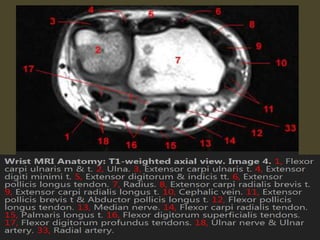

The transverse carpal ligament (short arrows) extends from the hook of the hamate (long

arrow) to the tubercle of the trapezium (arrowhead), forming the floor of the carpal tunnel.

At the radial aspect of the carpal tunnel, the flexor digitorum tendons are arranged in two

rows (separated by dotted line), the profundus tendons deep to the superficialis tendons. The

flexor pollicis longus tendon (star) is positioned at the ulnar aspect of the tunnel, separated

from the flexor carpi radialis tendon (curved arrow) by a ligamentous reflection of the

transverse carpal ligament. The median nerve is indicated (asterisk). - See more at:

http://radsource.us/palmar-bursae-and-flexor-tendon-sheaths/#sthash.mSFX1u0c.dpuf